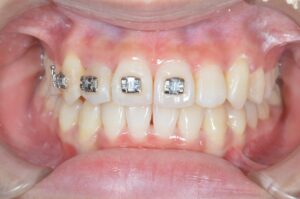

歯並びの変化

矯正前→現在の順で並べていきます。

約1年でこんなにきれいに並びました!

矯正前の自分が今の歯並びを見たら大喜びしていると思うのですが、欲深い私はきれいになるにつれて細かいところが気になり始めました。

具体的にどこが気になるかというと

・上の前歯が少し傾いている

・右上2番目の歯をもう少し前に出したい

・下顎に隙間があり物が挟まる

以上3点の改善と噛み合わせの調整のため、2回目の追加治療を行うこととなりました。